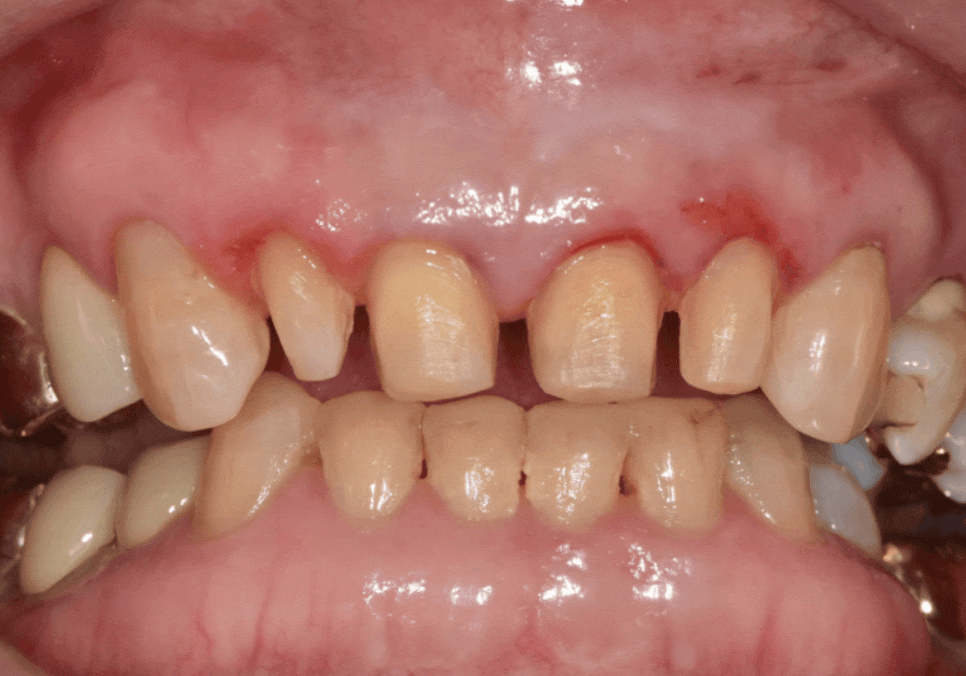

무삭제 라미네이트를 받을 수 있는 경우는

생각보다 훨씬 제한적입니다.

실제로는 대부분의 환자분들께 무삭제가 어렵고,

일부 치아 조건에서만 가능합니다.

대표적으로는 이런 경우에 해당됩니다.

치아가 원래 작은 경우(왜소치)

앞니 사이가 많이 벌어진 경우

치아 두께가 유난히 얇은 경우

치아가 안쪽으로 들어가 있는 경우

왜소치인 경우

치아 사이 공간이 넓은 경우

정리하면,

치아가 작거나 앞니 사이에 여유 공간이 있는 경우에는 치아를 많이 깎지 않아도 됩니다.

겉을 살짝 다듬는 정도만으로도

치아 크기와 모양을 자연스럽게 채워 넣을 수 있습니다.